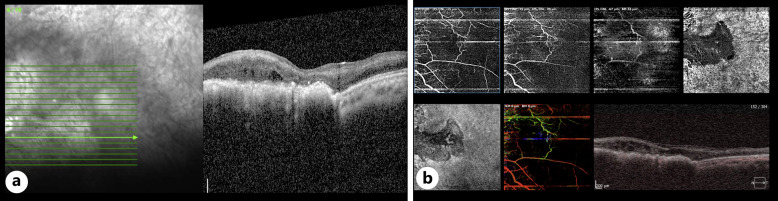

导言:抗磷脂综合征是导致获得性高凝状态的最常见原因之一,与眼部疾病有关,其中最重要的是动脉或静脉闭塞导致的视网膜缺血:我们描述了一例合并视网膜中央动脉和静脉闭塞并伴有视网膜色素上皮增生的单侧视网膜缺血病例。对患者进行了病因检查,发现是抗磷脂综合征:尽管色素上皮增生通常发生在视网膜缺血之后,但还没有研究报告对这种病理现象进行完整的多模态成像,也没有提出解释这种关联的可能机制。

Case presentation: We describe a case of unilateral retinal ischemia in the setting of combined central retinal artery and vein occlusion with associated proliferation of retinal pigment epithelium. The patient was worked-up for the etiology of her presentation which was found to be antiphospholipid syndrome.

Conclusion: Although pigment epithelial proliferation occurs commonly after retinal ischemia, no study has reported complete multimodal imaging of such a pathology or proposed the possible mechanisms explaining such an association.